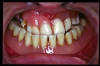

CM Falta de contactos interoclusales

CM Extrusión de incisivos inferiores por falta de contactos oclusales